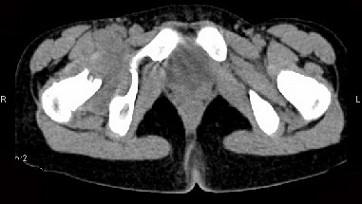

问题 女,11岁,肺部有结核病史,2个月前右髋关节有外伤史,右髋关节部逐渐肿胀疼痛,休息后可减轻,请结合所提供图像,选择最佳选项 ( )

选项 A、右髋关节类风湿关节炎 B、右髋关节痛风 C、化脓性骨关节炎 D、右髋关节退行性变 E、右髋关节结核

答案 E